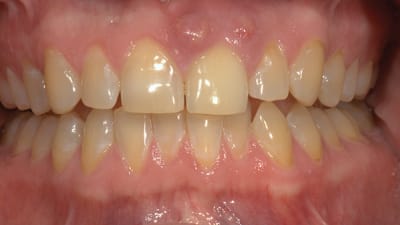

Kois Center Case Periodontics Oral Surgery Managing Ridge Resorption After Tooth Extraction Using Partial Extraction Therapy By Jeff H. Bynum, DDS February 01, 2018 13 min read